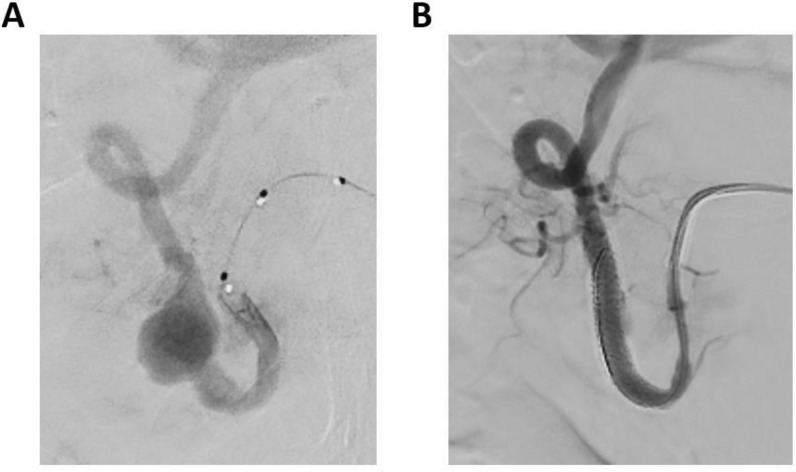

Hepatic artery aneurysms (HAAs) are rare vascular malformations that can arise from atherosclerosis, trauma, or iatrogenic injury. HAAs can be symptomatic and lead to serious complications. We present the case of a patient with painless jaundice caused by obstruction of the distal common bile duct by a HAA on a replaced right hepatic artery. This was further complicated with cholangitis. After endovascular stenting of the aneurysm, cholestasis decreased. Learning point: Hepatic artery aneurysms can cause common bile duct obstruction resulting in cholestasis.